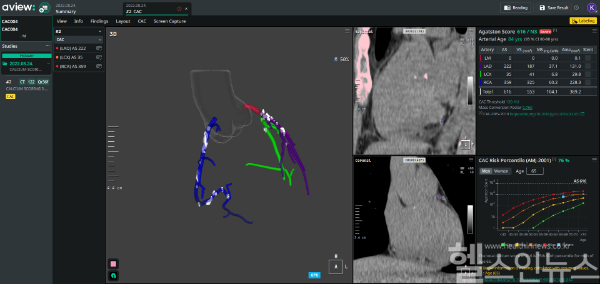

‘AVIEW CAC’는 저선량 흉부 CT 한 번으로 관상동맥석회화(CAC) 지수를 자동 분석해 심혈관 질환 위험을 조기에 평가한다. 국내 식약처 3등급 의료기기 인증과 미국 FDA 510k 승인을 받았으며, 미국대학심장학회지(JACC)에도 성능 우수성이 발표된 바 있다.